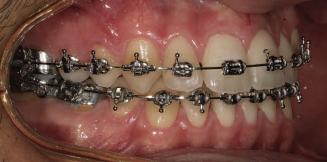

20 Dental Tribune Bulgarian Edition / октомври 2022 г. П ациентите със завършен растеж и скелетни проблеми обикновено представляват предизвикателство за ортодонт ската практика. Необходимостта от изваждане на зъби в комбинация с особеностите на възрастовата ортодонтия изисква особено внима ние. Фокусът върху критично важното значение на позицията на долните резци във връзка с дългосроч ната стабилност и постигането на оптимални оклузални взаимоотношения при затварянето на екстракционните пространства лесно може да излезе извън контрол. Когато към тези чисто кли нични проблеми се добави и стресът от натоваре ната практика, предизвикателството става още по-голямо. Всички тези фактори налагат използ ването на доказан подход с ясни и последовател ни стъпки, в което се разкрива силата на дисциплината „Алекзандър“ – предвидим протокол през целия процес на елиминиране на ротациите, ниве лиране на дъгите, затваряне на екстракционните пространства и финализиране на случая. Именно такъв е и случаят, който презентираме –екстракционен, скелетен клас 3 при възрастен па циент, лекуван по системата „Алекзандър“. ПРЕДВИДИМИ РЕЗУЛТАТИ ПРИ ПАЦИЕНТИ СЪС ЗАВЪРШЕН РАСТЕЖ И СКЕЛЕТЕН КЛАС 3, ИЗПОЛЗВАЙКИ ЕКСТРАКЦИОННО ЛЕЧЕНИЕ ПО ДИСЦИПЛИНАТА „АЛЕКЗАНДЪР“ Д-р Радой Димитров, България Преди започване на лечение клиничен случай | ортодонтия Фиг. 1а–1e Преди започване на лечение. Пациентът пристига в практиката с основното оплакване от невъзмож ност за нормално дъвчене. Снета е цялата необходима диагностична ин формация. Фиг. 1f–1h Снимки в профил и анфас. Фиг. 1i–1k Панорамна снимка, телерентгенография и анализ на телерент генография. Фиг. 1а Фиг. 1d Фиг. 1f Фиг. 1g Фиг. 1h Фиг. 1e Фиг. 1b Фиг. 1c Фиг. 1i Фиг. 1j Фиг. 1k

closed.

21Dental Tribune Bulgarian Edition / октомври 2022 г. ДИАГНОСТИЧНИ РЕЗУЛТАТИ: 1. Възраст на пациента: 21 години 2. Скелетен клас III (ANB 0) 3. Зъбен клас 3 4. Ръбцова захапка във фронта, кръстосана в дисталните участъци 5. Тясна горна челюст 6. Overjet – 0 мм, Overbite – 0 мм 7. Несъответствие на горната с долната средна линия 8. Единични контакти в ЦО 9. Хиподивергентен тип на растеж SN/MP – 33.5 10. Неравен гингивален контур 11. Неравна линия на усмивката 12. Тенденция за рецесии в долен фронт ПРЕПОРЪЧИТЕЛНО ЛЕЧЕНИЕ: Пълно ортодонтско лечение с метални брекети „Алекзандър“ Корекция на клас 3 захапката в областта на кучешките зъби с екстракция на първите пре молари в долна челюст Корекция на кръстосаната захапка в дистални участъци Коригиране на ръбцовата захапка във фронта Подобряване на ОJ и OB на пациента Стрипинг в долен фронт Подреждане на зъбите в горната и долната челюст Професионално хигиенизиране и профилактични дентални прегледи са препоръчителни на всеки 6 месеца. 1-ви месец След 1 месец са залепени брекети в горната челюст – поставена е еластична дъга. 016 NiTi. В долната челюст са елиминирани ротациите, поставена е стоманена дъга. 016SS, закалена с ток, и еластична верижка за затваряне на пространствата. 3-ти месец В долната челюст е поставена трета дъга – 17 x 25 NiTi с къси лигатури и верижка

В горната челюст се затварят пространствата с дъга .016SS и верижка. 5-и месец На 5-ия месец след залепяне на брекетите в долната челюст е поставена стоманена дъга 16 x 22 SS с четвъртито сечение, омега луп и тай бек. В горната челюст е поставена дъга 17 x 25 NiTi. Поради липсата на стабилни оклузални контакти са поставени лингвални верижки в областта на моларите, за да се предотврати нежелана ротация на 7-ите зъби. 6-и месец На 6-ия месец от началото на лечението са екстрахирани долните първи премолари, поставена е дъга 16 x 22 SS със затваряща чупка teardrop. Чупката се активира всеки месец по 1 мм с чинч-бек. клиничен случай | ортодонтия СТЪПКИ НА ЛЕЧЕНИЕТО Начало на лечението Лечението започва с поставяне на апарат за бърза експанзия в горната челюст. През първия месец от лечението са направени 24 оборота на апарата за експанзия. Залепени са брекети в долната челюст, поставена е дъга 17x25 CuNiTi, като са предпи сани клас 3 ластици (1/4”,4 1/2 oz) по време на сън, за да се осигури контрол върху торка на долните резци. Фиг. 2а Фиг. 3a Фиг. 4a Фиг. 3b Фиг. 4b Фиг. 3c Фиг. 4c Фиг. 3d Фиг. 4d Фиг. 3e Фиг. 4e Фиг. 5a Фиг. 5b Фиг. 5c Фиг. 5d Фиг. 5e Фиг. 6a Фиг. 6b Фиг. 6c Фиг. 6d Фиг. 6e Фиг. 7a Фиг. 7b Фиг. 7c Фиг. 7d Фиг. 7e Фиг. 2b Фиг. 2c Фиг. 2d